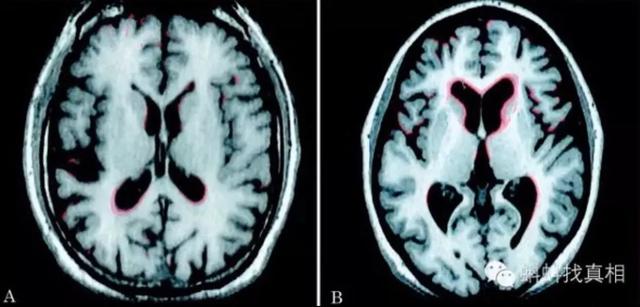

脳萎縮とは、様々な原因による脳組織自体の器質的な病変により、脳細胞の数や体積が減少し、形態学的に萎縮として現れる現象である。頭蓋CTやMRIでは、脳組織の容積の減少や脳室やクモ膜下腔の拡大が認められることがある。この疾患は50歳以上で発症する傾向があり、数年から数十年続くことがあり、女性よりも男性に多い。

脳萎縮は、疾患、外傷、腫瘍、遺伝性疾患、変性神経障害などによって引き起こされ、その結果、大脳ループの密度が低下し、脳室間の隙間が広がり、ループと頭蓋骨との距離が変化し、脳の容積が変化することが、通常のMRI追跡によって検出される。 脳萎縮は、身体機能のある程度の低下を意味すると考えている。また、脳梗塞や脳出血などの脳血管障害に罹患した患者も、諸機能のリハビリテーションがすぐに行われなかったり、放置されたりしていると、以前の画像診断で残された損傷の痕跡が増殖しているのがわかる。

脳萎縮は画像診断の一つであり、CTやMRIで灰白質の減少や溝の深化を認めた場合、画像診断医は「脳萎縮」と診断する。病理学的には、脳萎縮は脳組織の縮小、細胞数の減少、脳室とクモ膜下腔の拡大によって特徴づけられる。脳萎縮は必ずしも病的なものとは限らず、通常は生理的脳萎縮と病的脳萎縮がある。

1.生理的な脳の萎縮 年齢が徐々に高くなるにつれて、ほとんどの人の脳は、特に60歳以上の人は、脳溝の深化と脳回の狭小化によって現れる、さまざまな程度の萎縮が見られるようになる。しかし、これは人間の正常な老化の現れであり、通常、知能や記憶力、計算能力などの特別な低下は見られない。

2.病理学的脳萎縮 病理学的脳萎縮は通常60歳未満で発症し、その原因としては、1.脳卒中、外傷性脳損傷、頭蓋内感染による脳萎縮、2.アルツハイマー病、前頭側頭葉型認知症、ハンチントン病、皮質基底核変性症、多系統萎縮症、進行性核上性麻痺、その他の神経変性疾患による萎縮、3.長期にわたる過度のアルコール摂取、などが挙げられる。

脳萎縮の部位でいえば、大脳萎縮と小脳萎縮に簡単に分類できる。大脳は言語や思考などを司り、小脳は主に平衡感覚を司る。従って、大脳が萎縮すれば、判断力、思考力、言語表現力などにある程度の影響が出ますし、小脳が萎縮すれば、主に運動失調、バランス能力の低下、歩行が不安定になります。大脳萎縮であれ、小脳萎縮であれ、患者に大きな弊害をもたらし、重度の大脳萎縮は認知症にまで発展する可能性がある。